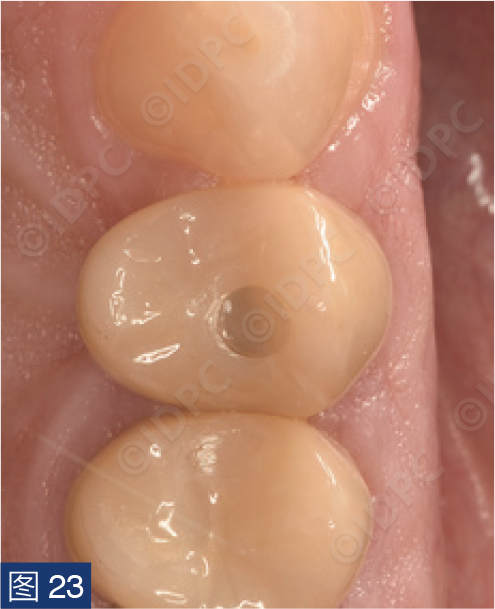

在exocad软件(exocad公司)上进行全数字化修复流程设计,在copaSKY uni.fit钛基底(bredent medical公司)上制作完成螺丝固位氧化锆混合陶瓷一体冠。种植位点显示出足够的颊侧软组织厚度(图12a)及良好的牙龈轮廓(图12b)。取下个性化愈合基台后,种植体周围软组织健康(图13、14),此外,取下后立即进行术前口内扫描以记录软组织轮廓。随后放置扫描体并进行数字印模以记录种植体位置(图15)。同时扫描对颌牙弓及咬合信息。获得的STL文件以数字方式发送至技工室。技工室在钛基底上完成聚甲基丙烯酸甲酯(PMMA)材料的试戴牙冠,以检查邻接和边缘密合情况,同时调整咬合(图16、17)。一旦完成所有调整,进行重新扫描。最终在钛基底上完成螺丝固位的全结构氧化锆混合陶瓷修复体,与牙龈接触的修复体表面高度抛光(图18),并以25 Ncm戴入口内。修复体实现了出色的颜色匹配及临床结果(图19)。螺丝孔用聚四氟乙烯填塞并用树脂材料密封(图20)。术后对照X线片显示修复体正确就位(图21)。六个月复查,增加的软组织轮廓清晰可见,牙槽骨水平保持稳定(图22-24)。

图19:最终修复体戴入后颊侧观,显示出完美的颜色及形态。

图20:树脂封闭𬌗面螺丝孔。